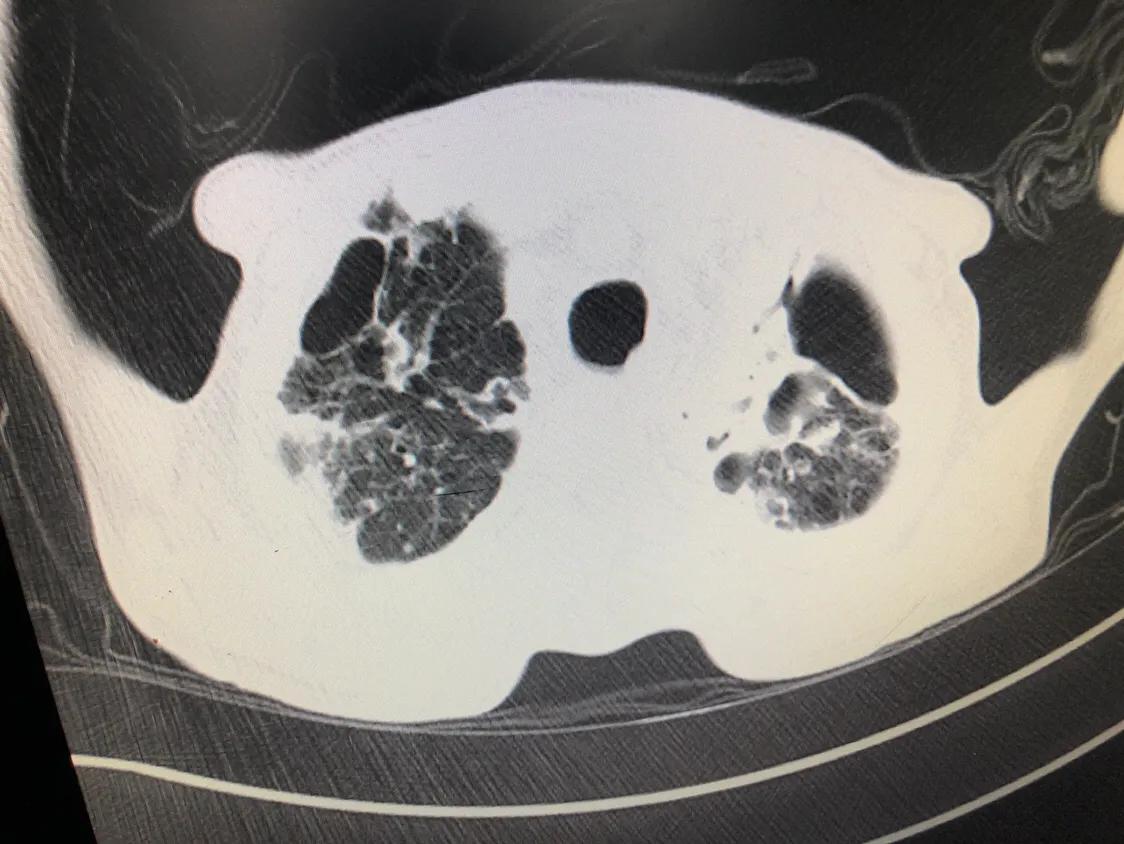

影像学检查包括X线胸片和胸部CT。前面讲的几种主要类型的肺结核,各自有不同的表现:

- 继发性肺结核是最常见的,其X线表现也是最复杂、多变的,有时很难跟普通的肺炎相鉴别。

CT相对于胸部X线片来说,会更清楚,分辨率更高,能看到更小的病灶,但存在着辐射比胸片更大的缺点。

肺部影像学检查,大多数情况下能提供基本准确的肺结核的诊断,但是仍然有少部分人需要完善进一步的检查,才能使结论更可靠。

诊断性抗结核治疗后,最好每个月检测一次肺部的X线片或者CT,如果病灶有吸收,说明结核的倾向更大;如果两个月没有任何吸收,则要重新考虑诊断。

- 胸片或CT显示与活动性肺结核相符的病变 ;